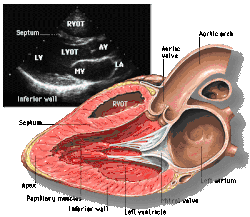

|  Subcostal four chamber |  Apical four chamber |  Parasternal long axis  |  Parasternal short axis  | ||||||||

| Each figure contains a TTE with a black background, and a corresponding colored illustration. | Patrick J. Lynch and C. Carl Jaffe, Yale University, 2006. | ||||||||||

| Click on a figure to enlarge it and see some parts of the heart identified. RV, right ventricle; LV, left ventricle; RA, right atrium; LA, left atrium; TV, tricuspid valve; MV, mitral valve; AV, aortic valve; RVOT, right ventricular outflow tract; LVOT, left ventricular outflow tract | |||||||||||